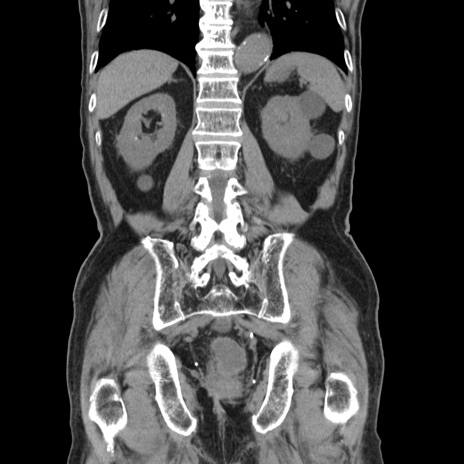

症例24(冠状断像)

【症例】80歳代男性

【主訴】左側腹部痛、嘔吐

【現病歴】本日早朝より左腹部に痛みあり。昼頃嘔吐認めたため、救急要請。

【既往歴】直腸癌(Mile手術)、胆摘

【身体所見】意識清明、BT 35.9℃、BP 221/93mmHg、SpO2 97%(RA) 、腹部:左ストーマ周囲に限局性の腹部膨隆あり。 膨隆部自発痛・圧痛あり・軟。

【データ】WBC 7700、CRP 0.09